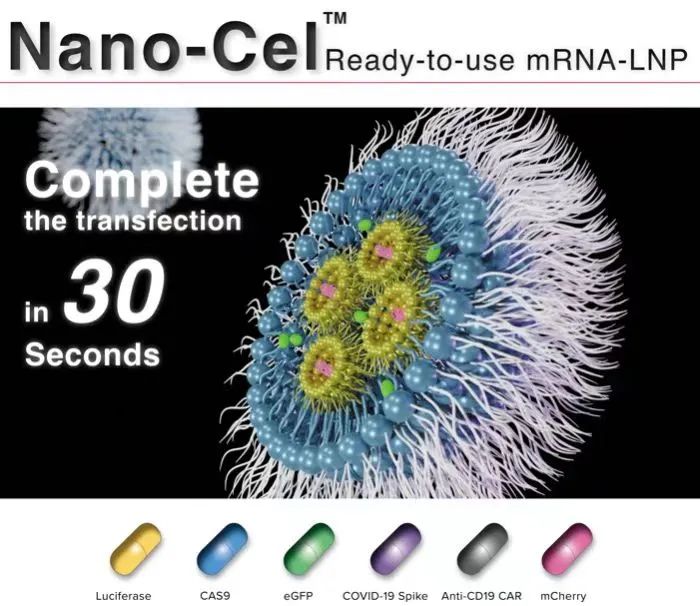

mRNA-LNP定制

依托在基因递送脂质纳米颗粒(LNP)的配方和制造方面的专业知识,开发下一代治疗方法,平台使用经过验证的mRNA递送系统,已经在制药行业取得了成功,并进一步提升了客户基因药物的应用深度。

好消息接踵而至!金年会|金年会·jinnian(金字招牌)诚信至上 新一代非病毒递送载体 mRNA-LNP的优势到底何在?

2024-07-08 15:31:25